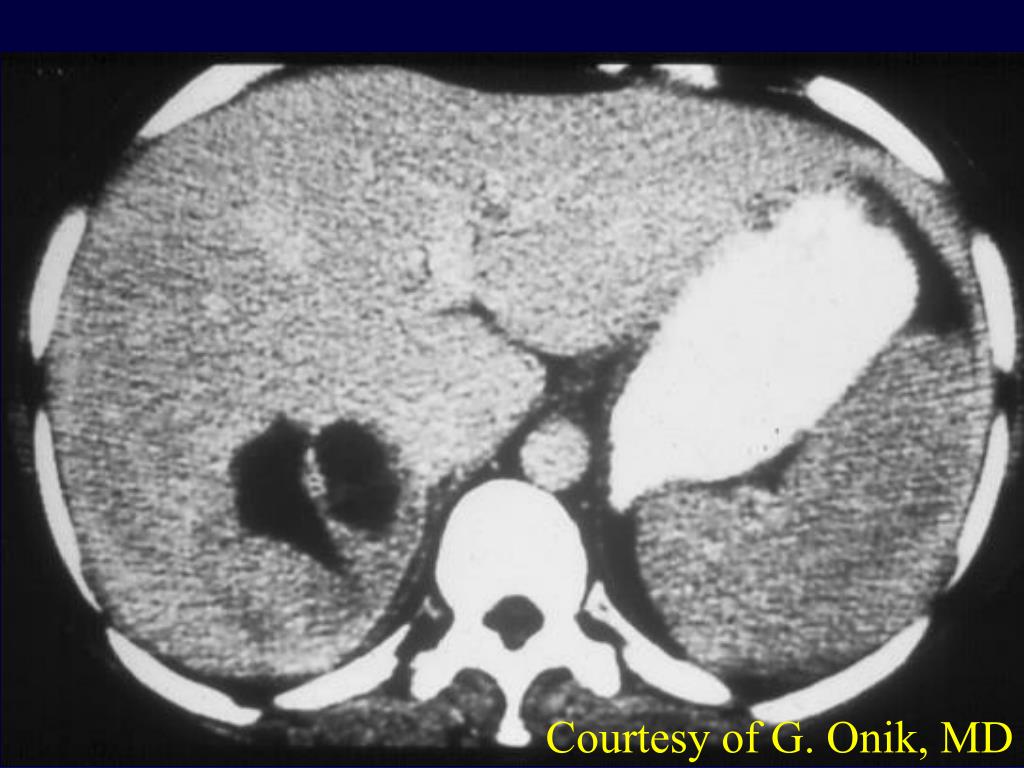

32. Cryoablation of liver tumors • First focal tumor ablation technology • Performed clinically since the early 1960’s • Combined with IOUS in 1980’s (Onik)

33. Courtesy of G. Onik, MD

34. In era of RF, is cryo still needed? • Very powerful. Multiple probes make a large iceball in a short period of time, can ablate up to large vessels.